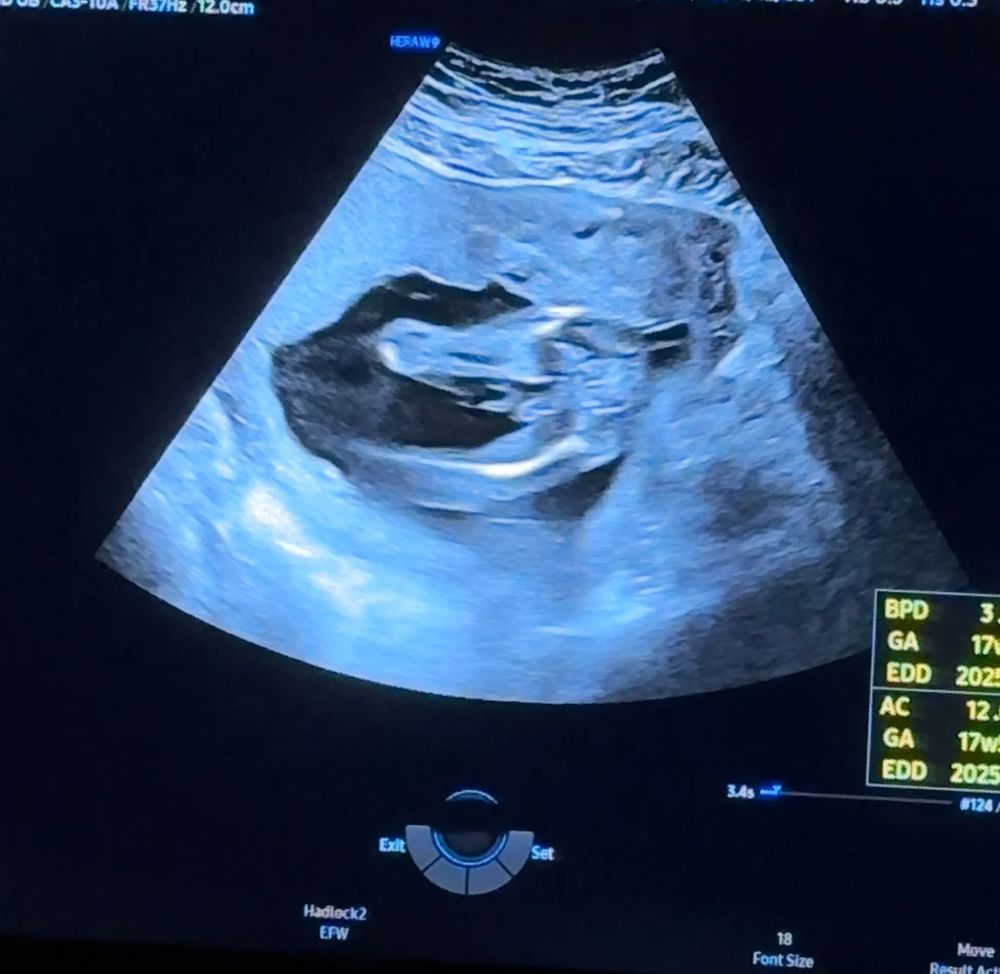

Севара, нет, нам с мужем тогда было не до фоток) сидели все в мониторах узи😁 но там прям чётко видно две ножки и половой орган, а у девочек говорят кофейное зёрнышко. Если на втором фото две ножки то там вроде как это зёрнышко есть)

Евгения, кажется это то самое, что торчит. Не похоже на пуповину. Я думала просто девочка и так уверена была, а у нас тут писююн 🥹🥹🙈🙈🥰🥰

Севара, а, ну на этом фото конечно видно😁 а на двух из поста такой детализации нет) это естественно мальчик😁 поздравляю 🥳

Евгения, Скорее всего я неправильно заскринила, не понимаю же. А смотрю хорошенько что то торчащее увидела 😄😄. Спасибо большое 🥰🥰